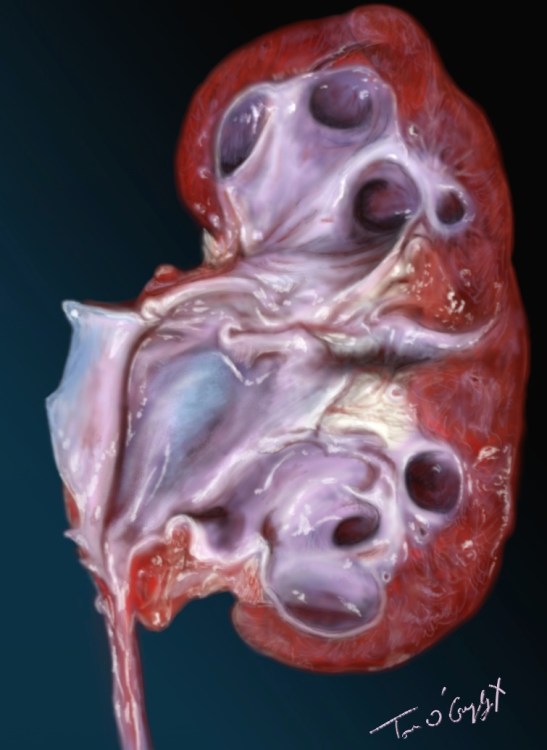

hydronéphrose sur une pièce autopsique d’un rein coupé en 2 avec dilatation des cavités pyélo-calicielles

Dans les autres cas la crise sera compliquée d’obstruction qui menace par augmentation de la pression en amont, de détruire le parenchyme rénal (hydronéphrose), et secondairement d’infection urinaire, la stagnation des urines et la nature de la lithiase favorisant la prolifération bactérienne, autre cause de destruction rénale et de septicémie.

Une colique néphrétique fébrile (qui plus est en choc septique), accompagnée d’insuffisance rénale ou persistante sur plusieurs heures d’autant plus que l’antalgie n’est pas efficace doit faire pratiquer une échographie pour rechercher la dilatation des cavités pyélo-calicielles, et une urographie intraveineuse ou actuellement plutôt un uroscanner qui permettent en plus la visualisation du siège de l’obstacle avant traitement urologique.